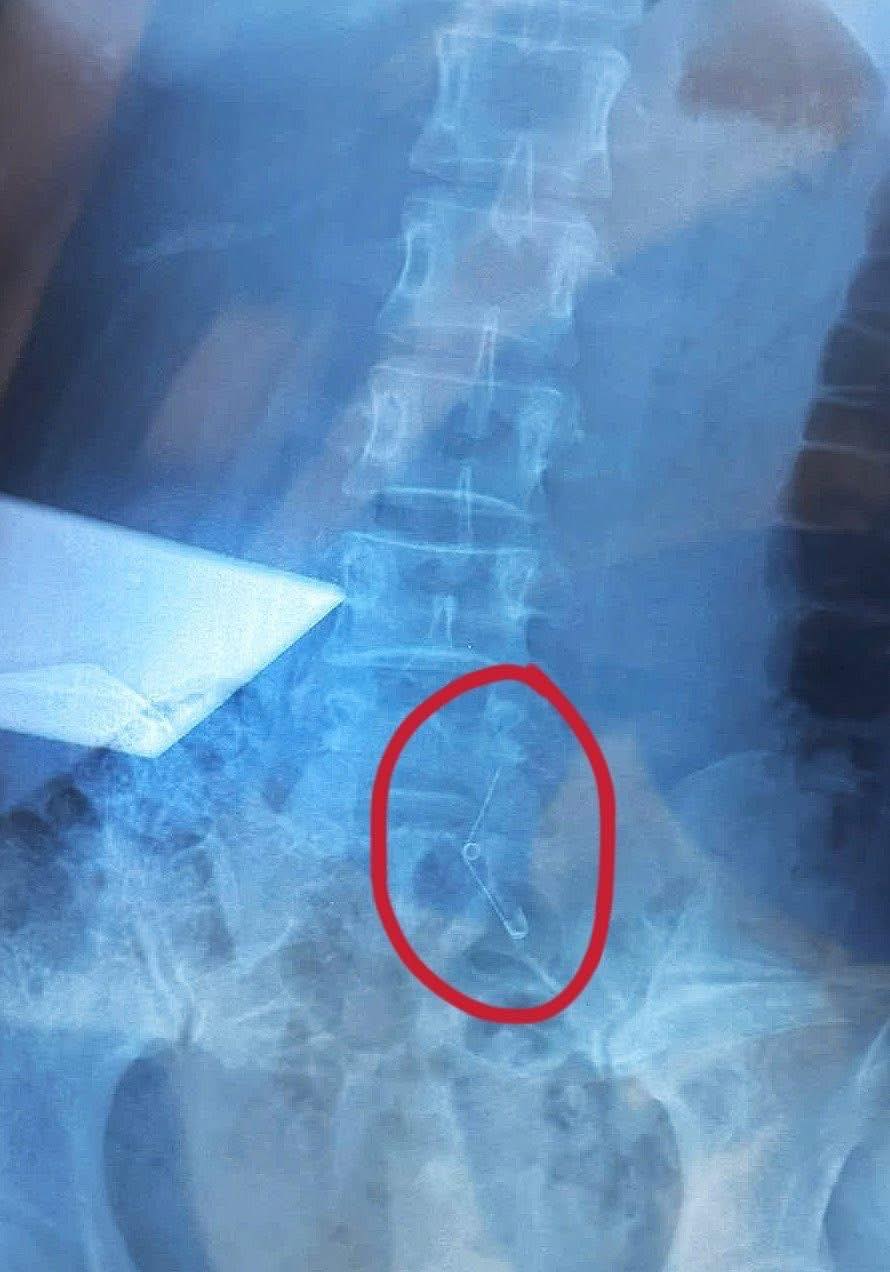

Trong một tình huống khó tin nhưng có thật, một người phụ nữ đã gặp phải sự cố hy hữu khi đang thưởng thức món ốc cùng đồng nghiệp. Trong lúc ăn, cô bỗng cảm thấy nghẹn nhưng vẫn tiếp tục ăn uống bình thường. Đến khi nhìn xuống và không thấy chiếc ghim băng khêu ốc đâu, cô mới hoảng hốt nhận ra rằng mình đã nuốt nó vào bụng.

Ngay trong đêm, nạn nhân đã được đưa đến bệnh viện và trải qua gần 6 tiếng đồng hồ để các bác sĩ tiến hành mổ dạ dày nhằm lấy kim ra. Rất may, chiếc ghim chưa kịp gây rách thực quản.

Sao mổ dạ dày mà sao phim chụp lại nằm ở dưới khung chậu thế nhỉ, dạ dày to thế